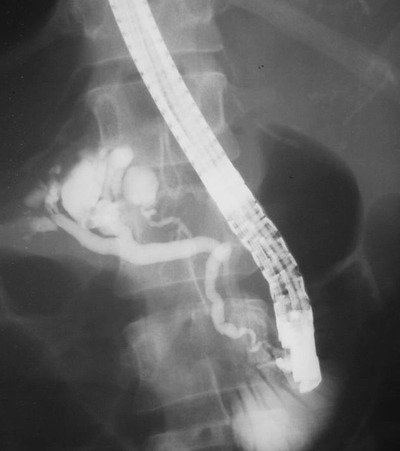

ERCP

ERCP报告:胰管全程扩张,横径约0.4~0.5cm,管壁欠光整,胰体见一直径约3.5cm囊性多房性占位,与胰体段胰管相通——胰体囊性多房性占位(可疑粘液产生)

十二指肠乳头增大,扩张,见黏液流出。